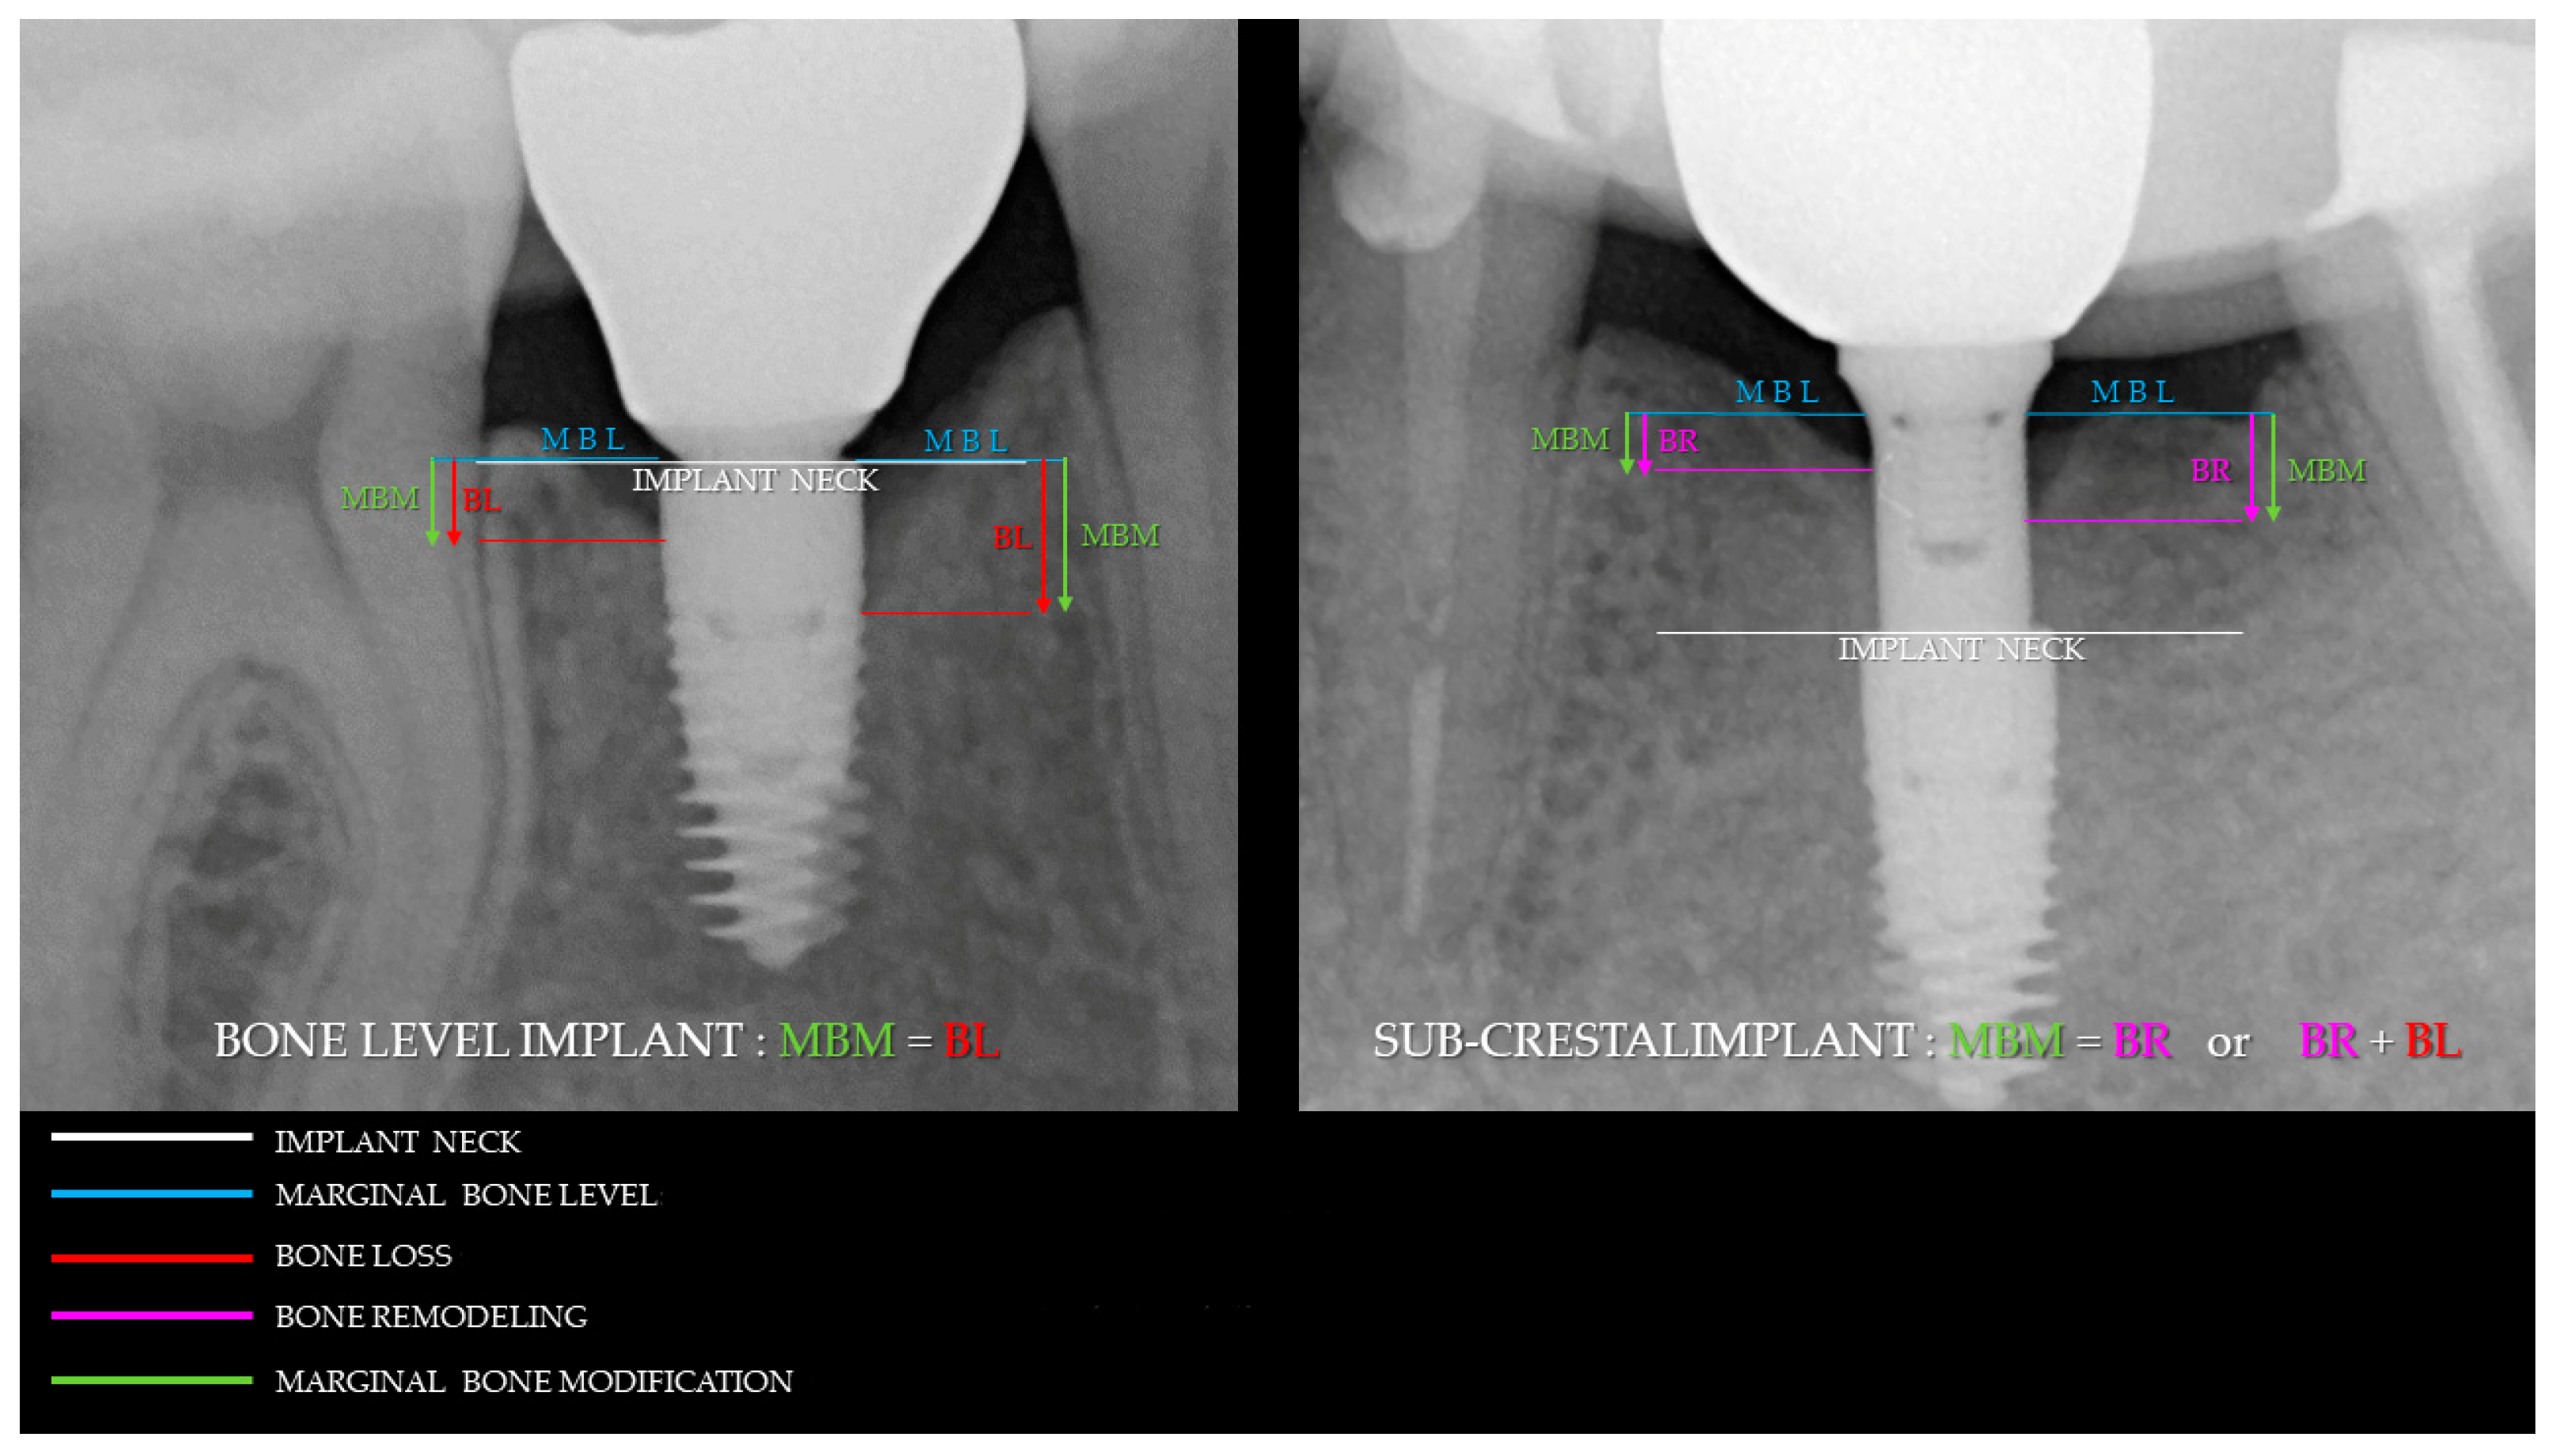

2.4. Radiographic Evaluations